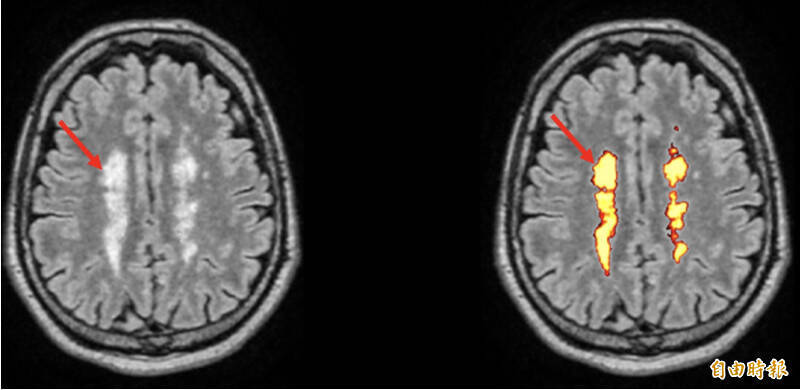

第7名:台灣人特有危險基因 48歲後腦部快速病變易失智、中風

新聞摘要:台灣人有一特殊的危險基因變異,容易導致中風及失智,帶因者盛行率約1%,先天血管壁較脆弱,年輕時就可能出現腦病變,腦部白質病變風險快速增加,認知功能可能已經下降,卻無明顯症狀,提醒有中風家族史及高血脂等腦心血管問題者,必須提早警覺。